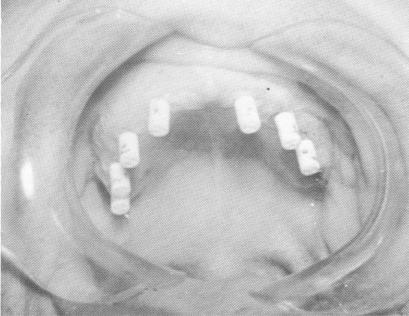

Fig. 10-215. Pin implants in series of three's were driven through the marked areas and into the bone. Their ends were then bent parallel to one another and their excess length removed. (Courtesy I. Lew.)

4 Dental pin implants in series of three`s were driven into the bone